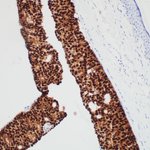

Endocrine mucin-producing sweat gland carcinoma of eyelid. What needs to be ruled out here? 1. Ink on paper 2-3. H&E 4. PR #neuropath #neuropathology #eyepathology #ophthalmology #inktober #inktober2022